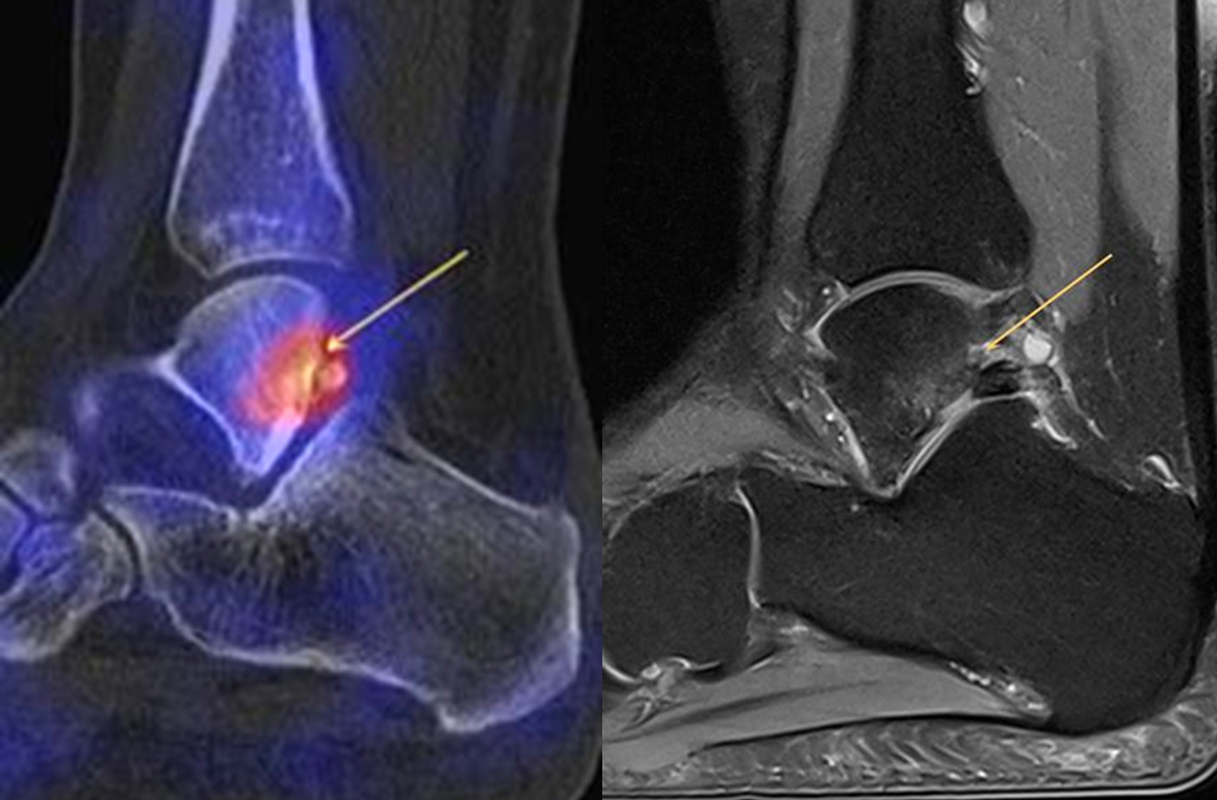

Abbildung 2.1.

Bildbeispiele symptomatische OCL

Zum Lesen der Bildbeschreibung und zur Vollansicht bitte das Bild anklicken. Bild: H. C. Rischke

Abbildung 2.2.

Bilder eines Patienten mit Z. n. mehrfachen Sprunggelenksdistorsionen in der Vergangenheit, besonders heftige Distorsion des linken Sprunggelenkes 5 Wochen vor der Untersuchung. Die SPECT/CT zeigt eine instabile osteochondrale Läsion mit deutlicher Aktivierung.

Abbildung 2.3.

Klärung bei Schmerzen im rechten OSG bei OCL an der medialen Talusschulter. Z. n. OSG-Distorsion vor 2 Jahren und Z. n. OSG-Fraktur / Syndesomosenruptur. Ausgedehnte OCL, hier jedoch kein erhöhter Knochenmetabolismus; lediglich Nachweis einer Stressreaktion im Bereich der Synchondrose eines Os trigonum als Schmerzursache.